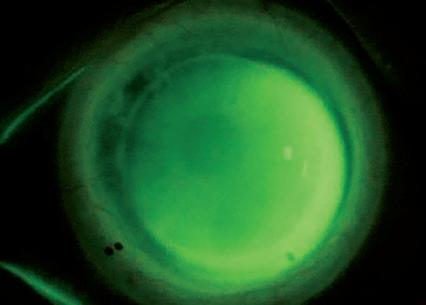

LES LENTILLES SCLÉRALES PERMÉABLES À L’OXYGÈNE CONSTITUENT UNE OPTION PRÉCIEUSE POUR LES CLIENTS QUI ONT SUBI UNE TRANSPLANTATION CORNÉENNE. APRÈS UNE KÉRATOPLASTIE PÉNÉTRANTE (KP), ON MESURE TOUTEFOIS SOUVENT UNE TORICITÉ CORNÉENNE PRONONCÉE. CETTE SITUATION COMPLIQUE L’ADAPTATION DES LENTILLES SCLÉRALES.

Un homme de 53 ans est envoyé pour une adaptation de lentille sclérale après une greffe de cornée de l’œil gauche pour kératocône. La demande porte sur l’amélioration de la vision de l’œil gauche. L’acuité visuelle non corrigée OS est de 0,05. Avec une correction lunettes de + 1,25 –7,00 x 25, l’acuité atteint 0,50. Une adaptation diagnostique est réalisée avec une lentille sclérale Zenlens® (Bausch + Lomb) avec les paramètres suivants : courbure de base (BC) 7,42 mm, diamètre 15,4 mm, hauteur sagittale (SAG) 4600 µm et APS flat 2 x steep 2. La sur-réfraction est de plano –4,00 x 25. L’évaluation de l’adaptation montre un soulèvement de bord supérieur nasal, compatible avec un ajustement légèrement trop plat. On observe également une décentration inférieure temporale. La valeur cylindrique élevée à la sur-réfraction indique une flexion de lentille induite par la toricité. Le motif à la fluorescéine révèle des variations nettes de clearance, compatibles avec une cornée fortement torique (Figure 1A). En présence d’une toricité cornéenne importante, une voûte insuffisante dans certains méridiens peut provoquer un contact cornéen apparent. L’approche classique consiste à choisir un diamètre plus grand ou une hauteur sagit

ŒIL POST-KP PRÉSENTANT UN ASTIGMATISME CORNÉEN PRONONCÉ

tale plus élevée afin de couvrir l’ensemble de la cornée. Une autre option consiste à ajouter de la toricité au profil postérieur de la lentille afin d’obtenir une forme plus conforme à la géométrie cornéenne et une clearance plus homogène.

DISCUSSION

L’ajout de toricité au segment de la lentille situé entre la zone optique et la zone d’appui permet un meilleur alignement sur la cornée, tout en préservant une courbure de base sphérique et, si nécessaire, une puissance sphérique. Cette technique porte le nom de Bi-Elevation. Elle repose sur l’utilisation de deux hauteurs sagittales différentes, en correspondance avec les deux méridiens principaux de la cornée. L’évaluation de l’adaptation impose l’analyse de la clearance centrale dans les deux méridiens principaux. En cas de clearance centrale suffisante, l’ajustement de la SAG peut concerner un seul méridien. En cas de clearance insuffisante, il convient d’augmenter ou de réduire la SAG dans un ou dans les deux méridiens. Il faut également adapter la courbure de base afin d’optimiser l’alignement cornéen, en cohérence avec les modifications de la SAG. Dans ce cas, la mesure après stabilisation montre une clearance centrale de 211 µm. La valeur SAG existante de 4600 µm s’avère suffisante pour le méridien le plus plat. Afin d’obtenir une clearance supplémentaire entre 4–5 heures et 10–11 heures, la courbure de base globale passe de 7,42 mm à 8,04 mm, ce qui correspond à environ 3,5 dpt. Pour optimiser l’adaptation dans le méridien le plus cambré et améliorer l’appui, 200 µm de hauteur sagittale supplémentaire sont ajoutés. La lentille présente alors des valeurs Bi-Elevation SAG de 4600 x 4800 µm. Cette adaptation rend la zone SmartCurve® et les zones de clearance limbique plus cambrées dans le méridien le plus profond. Elle assure une clearance mi-périphérique plus régulière et un appui plus stable et homogène sur l’ensemble du pourtour de la lentille. La lentille définitive présente les paramètres suivants : BC 8,04 mm, SAG 4600 x 4800 µm, diamètre 15,4 mm et APS standard. L’évaluation de la nouvelle lentille montre un motif à la fluorescéine approprié avec un bon alignement et conserve la même position de rotation que la lentille APS torique précédente (Figure 1B).

Une toricité cornéenne prononcée complique l’adaptation des lentilles sclérales et peut entraîner une décentration, un prolapsus conjonctival ainsi que des zones de clearance excessive ou insuffisante. L’utilisation d’un design Bi-Elevation permet de compenser la toricité cornéenne au niveau de la voûte sagittale. Cette approche conduit à une adaptation sclérale mieux alignée et plus stable.